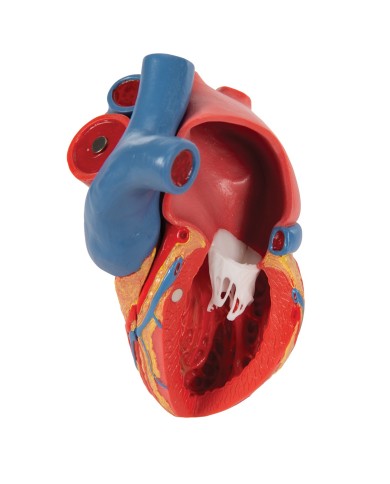

Modello di cuore di alta qualità scomponibile in 5 parti

Modello di cuore di alta qualità scomponibile in 5 parti

La parete anteriore del cuore è staccabile per poter vedere i ventricoli.

Realizzato in stampa 3D ad elevatissima risoluzione a colori.